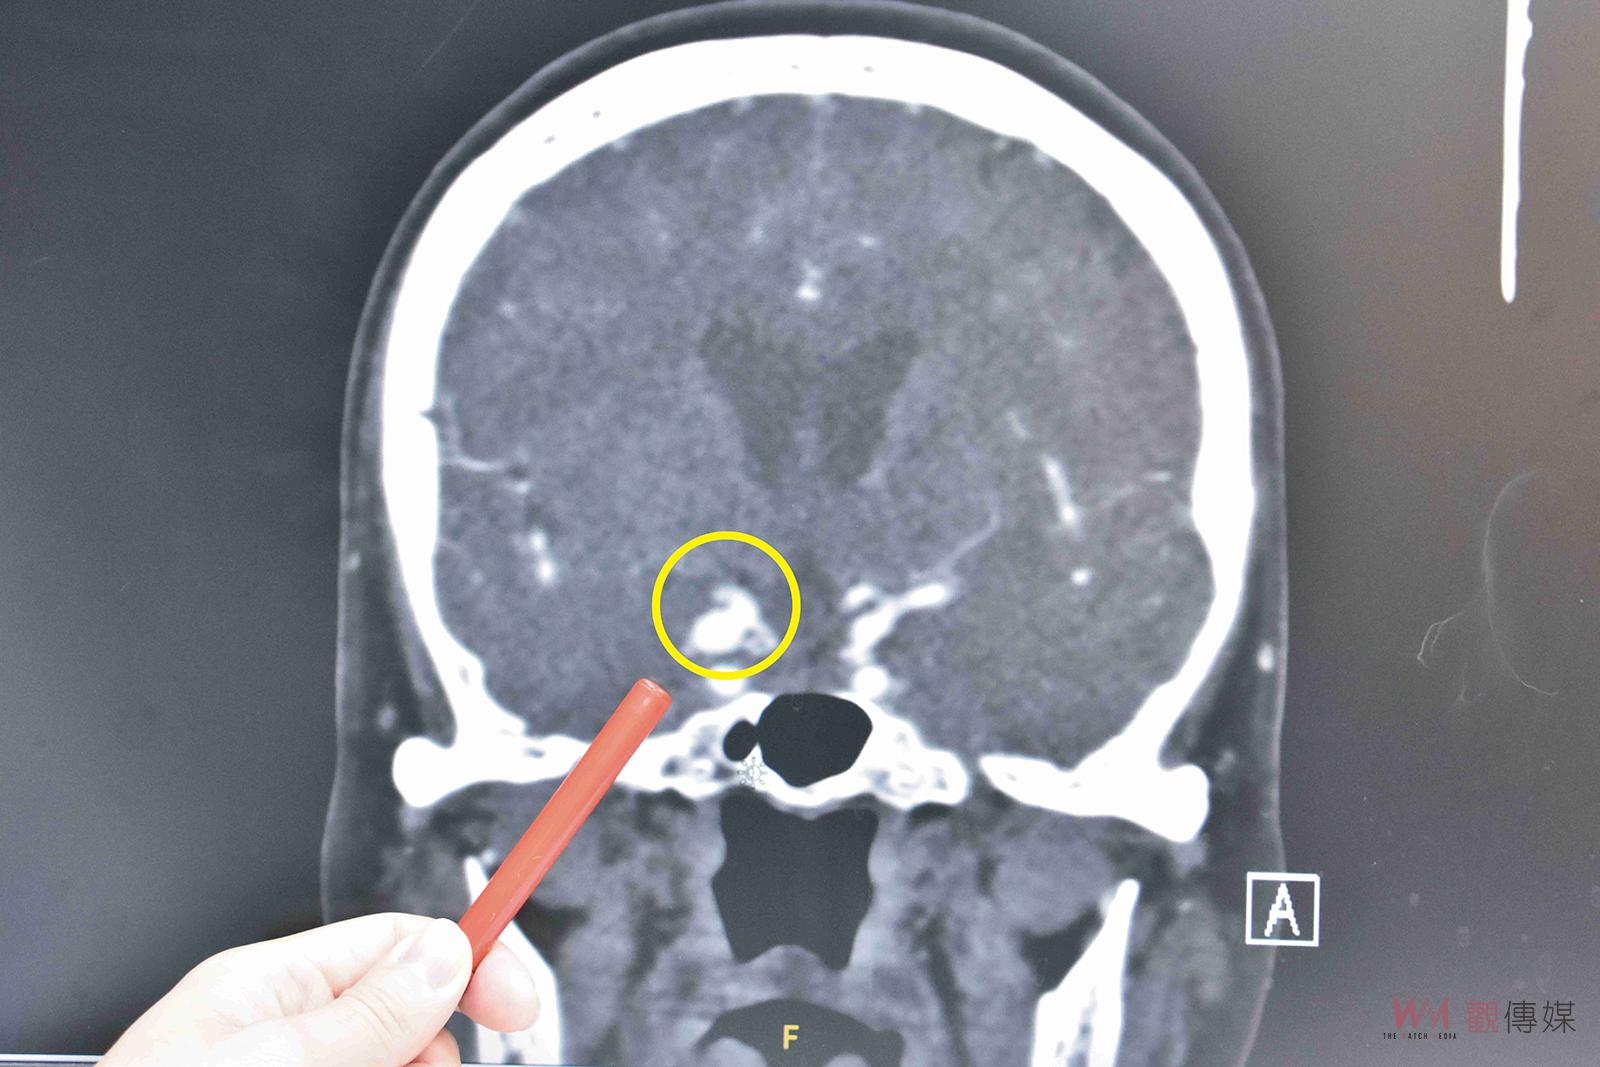

▲曾姓婆婆的動脈瘤有壓迫到視神經或動眼神經,在破裂出血造成昏迷前及時發現,可以早期處理。

(彰基醫院提供)

收治此病例的彰基神經外科主治醫師郭明錡表示,顱內動脈瘤雖有「瘤」字,但並非惡性腫瘤,不會擴散或轉移,也無法透過抽血篩檢發現。動脈瘤是因血流衝擊導致腦血管側邊或末端異常膨大形成的,屬於潛伏性殺手。大部分患者終生無症狀,只有少數如曾婆婆般,因動脈瘤壓迫視神經或動眼神經在破裂出血前及時發現,可以早期處理。大部分病人是在動脈瘤破裂後出現劇烈頭痛、意識不清等症狀才緊急送醫。